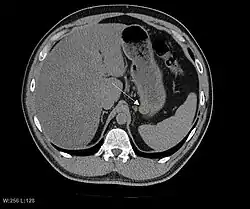

The purpose of radiologic imaging is to locate the lesion, evaluate for signs of invasion and detect metastasis. Features of GIST vary depending on tumor size and organ of origin. The diameter can range from a few millimeters to more than 30 cm. Larger tumors usually cause symptoms in contrast to those found incidentally which tend to be smaller and have better prognosis.[4][20] Large tumors tend to exhibit malignant behavior but small GISTs may also demonstrate clinically aggressive behavior.[21]

Barium fluoroscopic examinations and CT are commonly used to evaluate the patient with abdominal complaints. Barium swallow images show abnormalities in 80% of GIST cases.[21] However, some GISTs may be located entirely outside the lumen of the bowel and will not be appreciated with a barium swallow. Even in cases when the barium swallow is abnormal, an MRI or CT scan must follow since it is impossible to evaluate abdominal cavities and other abdominal organs with a barium swallow alone. In a CT scan, abnormalities may be seen in 87% of patients and it should be made with both oral and intravenous contrast.[21] Among imaging studies, MRI has the best tissue contrast, which aids in the identification of masses within the GI tract (intramural masses). Intravenous contrast material is needed to evaluate lesion vascularity.

Preferred imaging modalities in the evaluation of GISTs are CT and MRI,[23]: 20–21 and, in selected situations, endoscopic ultrasound. CT advantages include its ability to demonstrate evidence of nearby organ invasion, ascites, and metastases. The ability of an MRI to produce images in multiple planes is helpful in determining the bowel as the organ of origin (which is difficult when the tumor is very large), facilitating diagnosis.